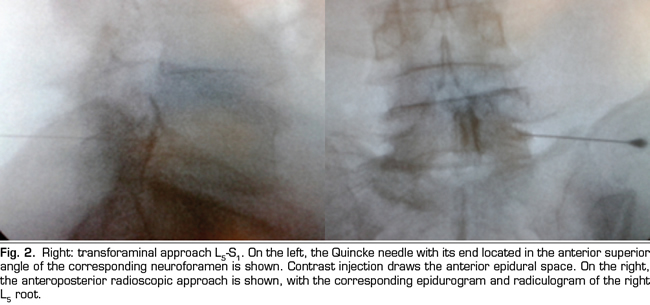

The final position of the needle in the oblique view was the subpedicular zone, while in the lateral view was the anterior superior angle or the roof of the neuroforamen, in the so-called safety triangle (Figure 2). The contrast volume injected was equivalent to the performed in the interlaminar group, obtaining a radiculogram and epidurogram after the injection (Figure 2). The solution of betamethasone was the same used in the interlaminar group, injecting the total volume of the solution in one or two levels, depending on clinical criteria.